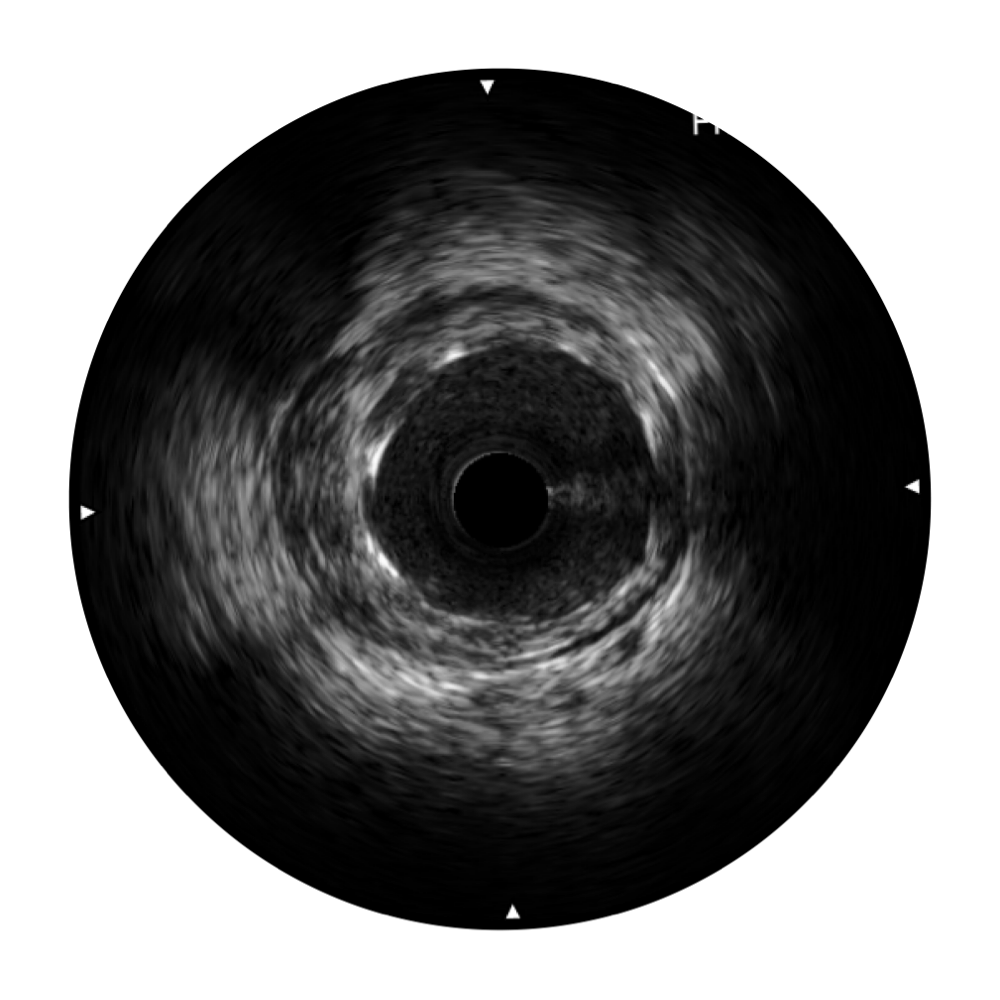

• 银河优越会宽频IVUS图像

对比传统IVUS导管成像,银河优越会宽频IVUS图像的近场支架梁显影更细腻,远场中膜外血管仍清晰可辨,兼顾远中近,兼顾分辨力与穿透深度